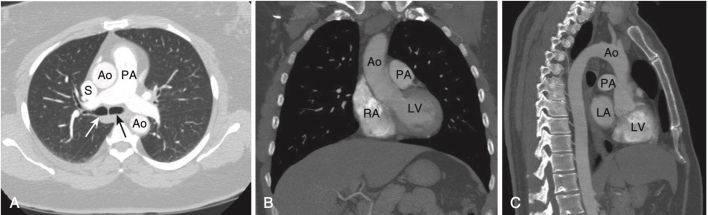

GIẢI PHẪU CT BÌNH THƯỜNG CỦA PHỔI

- Tất cả các giải phẫu có thể nhìn thấy trên phim X quang ngực thông thường đều quan sát được trên phim chụp CT ngực, nhưng với độ chi tiết hơn. Với việc tái tạo các hình ảnh CT lát cắt mỏng, phổi có thể được hình dung ở bất kỳ mặt phẳng nào, mặc dù ba mặt phẳng phổ biến nhất là mặt phẳng ngang (axial), mặt phẳng đứng dọc (sagittal) và mặt phẳng trán (coronal, còn gọi là mặt phẳng vành) (Hình 11).

- Các mạch máu: Có thể nhìn thấy gần như toàn bộ đường đi của chúng từ rốn phổi đến bề mặt màng phổi. Có thể phân biệt các động mạch phổi với các tĩnh mạch phổi (Hình 12).

- Các phế quản và tiểu phế quản cũng có thể nhìn thấy được, và theo quy luật, các phế quản thường nhỏ hơn các động mạch phổi đi kèm (Hình 13).

- Khí quản, thường có hình bầu dục, có đường kính khoảng 2 cm.

- Ở hầu hết mọi người, có một khoảng trống có thể nhìn thấy ngay dưới cung động mạch chủ nhưng ở trên động mạch phổi được gọi là cửa sổ chủ – phổi (aortopulmonary window, APW) (lưu ý không nhầm với cửa sổ chủ phế là một thuật ngữ để chỉ khiếm khuyết vách chủ – phổi bẩm sinh hiếm gặp). Cửa sổ chủ phổi là một mốc quan trọng, vì đây là vị trí phổ biến xuất hiện các hạch bạch huyết. Ở ngang mức hoặc thấp hơn một chút, khí quản chia đôi ở đường gờ giữa (carina) thành các phế quản chính bên phải và bên trái (Hình 14).

- Thấp hơn một chút là phế quản chính phải và trái và các phế quản trung gian. Phế quản chính bên phải có hình dạng một cấu trúc hình tròn, chứa khí và sẽ trở thành hình ống khi phế quản thùy trên bên phải xuất hiện. Sau phế quản trung gian không có gì ngoài mô phổi (Hình 15).

- Phế quản chính bên trái sẽ có dạng hình tròn chứa khí ở bên trái.